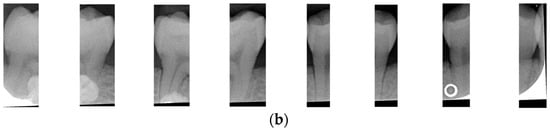

After dividing the BW into upper and lower rows of teeth, each tooth is segmented individually. Vertical projection and vertical erosion are used to find the troughs (y-minimum) of the adjacent waveforms, identifying the gaps between teeth to separate each one. The number of vertical lines required varies with the number of teeth in each row. If the number of teeth is n, then n − 1 vertical lines are needed for complete segmentation. These n − 1 lines correspond to the number of troughs found in the vertical projection of the waveform. The x-coordinates of these troughs are returned to the original image, where vertical lines are drawn to isolate the teeth. The peaks and valleys are marked with red circles in Figure 6a,b, which is shown in Figure 6c,d. Because secondary caries mainly occurs on both sides of the teeth, and since each complete tooth has both a left and right half, this increases the complexity during training and judgment, resulting in poor training outcomes. Therefore, each tooth image is further divided into left and right halves, as shown in Figure 7. This approach reduced the complexity of the data and doubled the training dataset, providing more data for training.

Figure 7.

Half-a-tooth training image. (a) The upper teeth (b) The lower teeth.